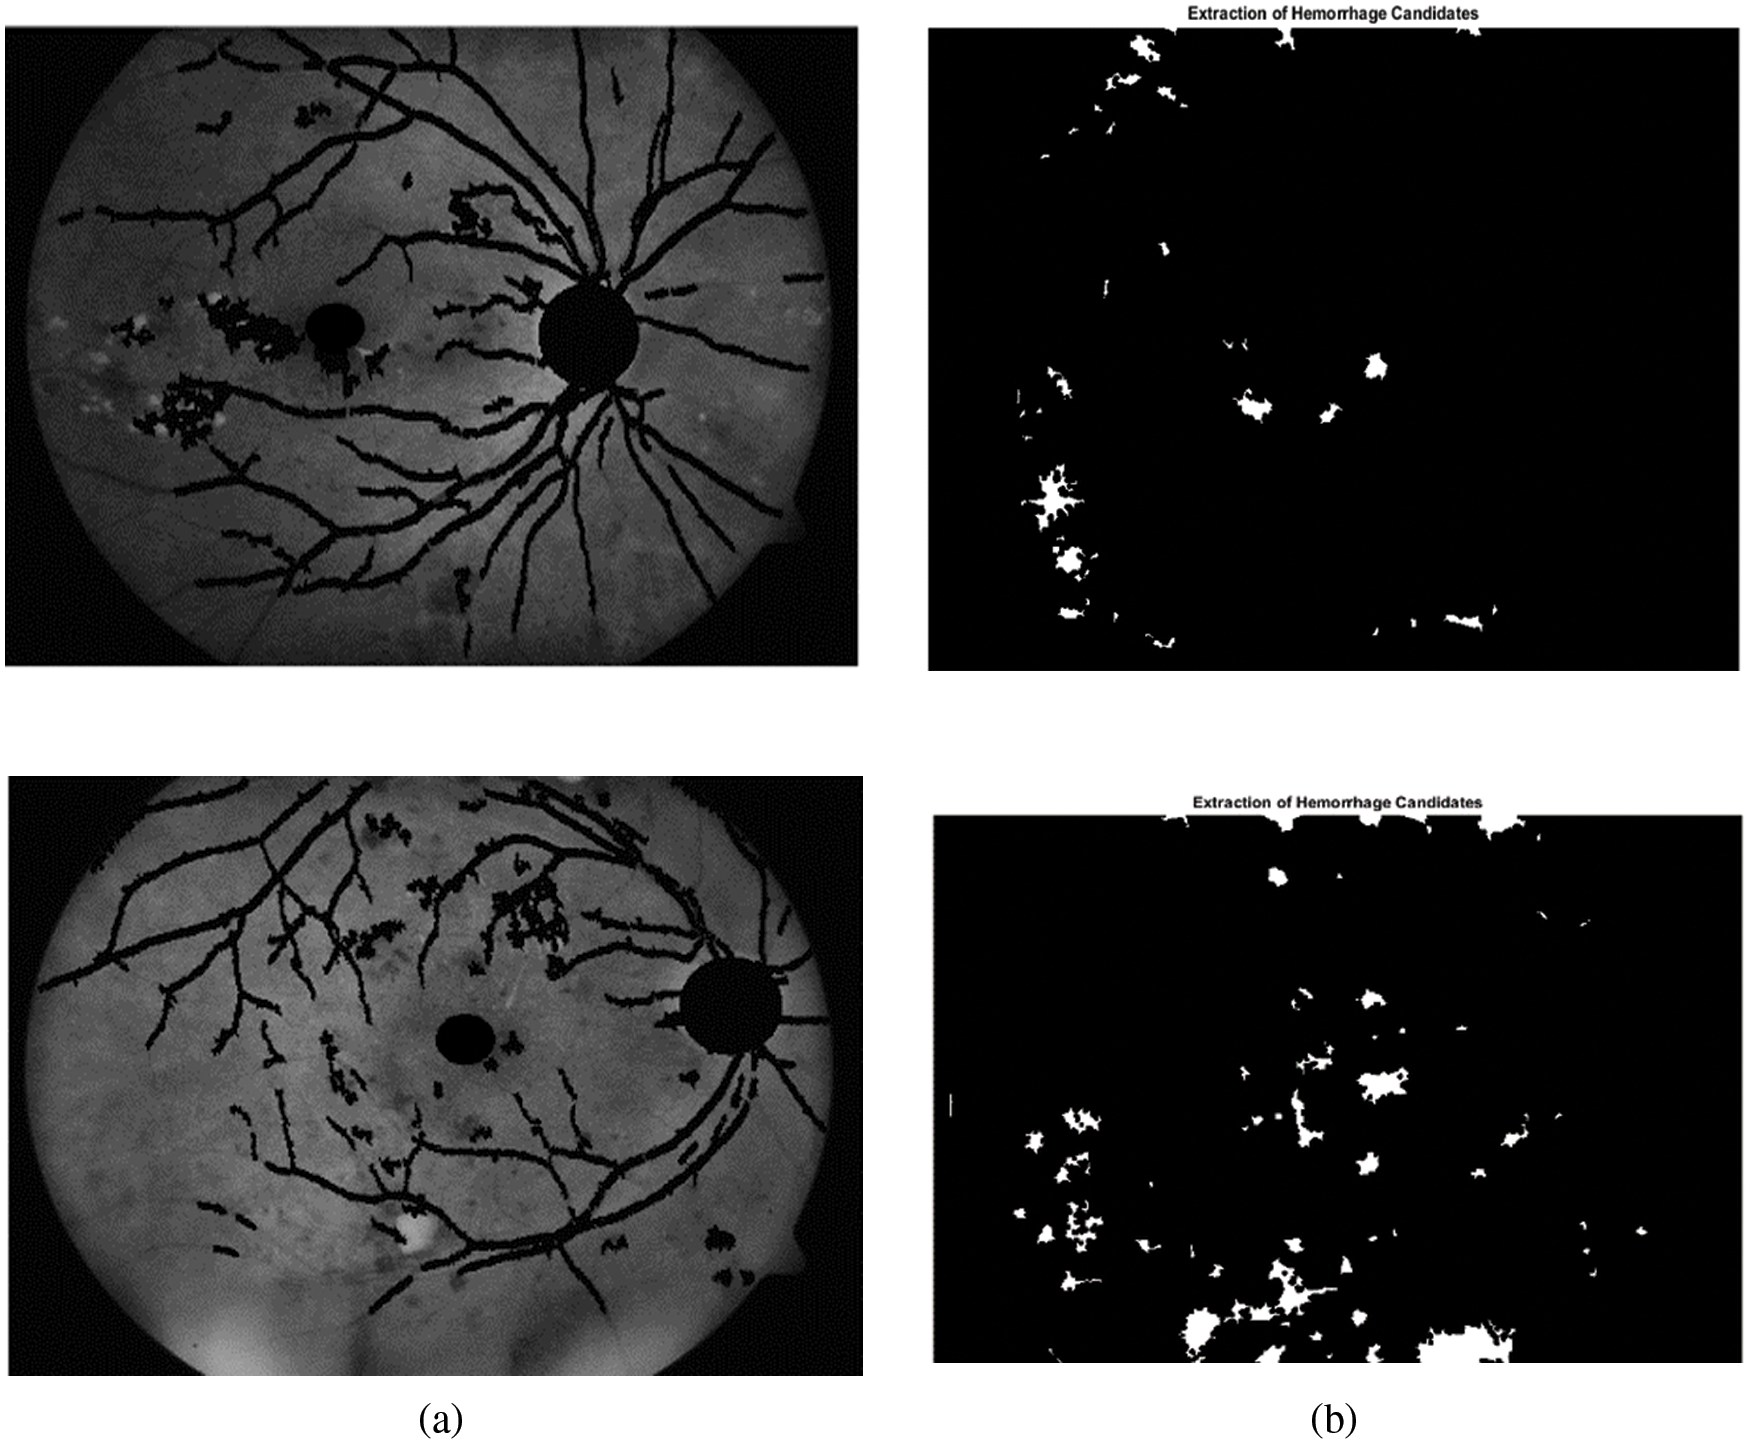

From Tab. 2 it is evident that the proposed method achieves better performance than the other methods with respect to average sensitivity for segmentation of optic disc. Fig. 7 shows green channel retinal images after masking normal objects and the candidate region of hemorrhages.

Figure 7: Extraction candidates region of hemorrhages. (a) Green channel retinal images after normal objects. (b) Candidates region of hemorrhages